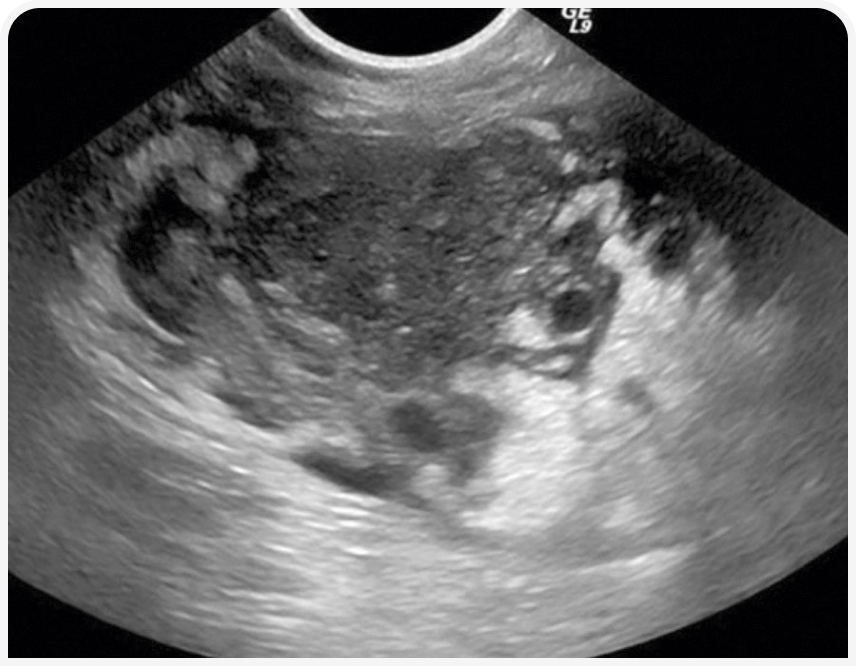

При рентгенографии органов грудной клетки можно выявить четко визуализируемое объемное образование в средостении (Рисунок 1), хотя иногда значительный плевральный выпот может затруднить визуализацию или сделать ее невозможной до тех пор, пока его не дренируют (Рисунок 2), поэтому могут потребоваться повторная рентгенография или УЗИ (Рисунок 3).